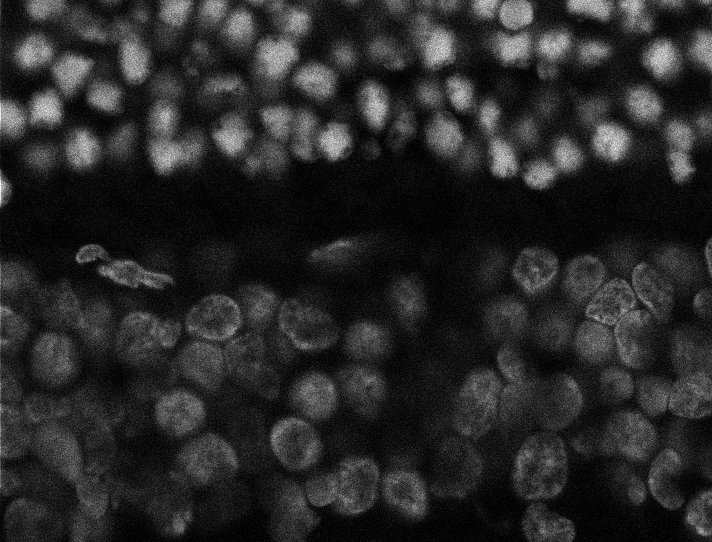

Nuclei

Nuclei - Bis